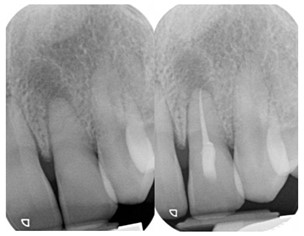

Secondary root canal treatment

Injury to the tooth can cause the root canal to shrink. High magnification and fine ultrasonic instruments are used to locate the root canal.